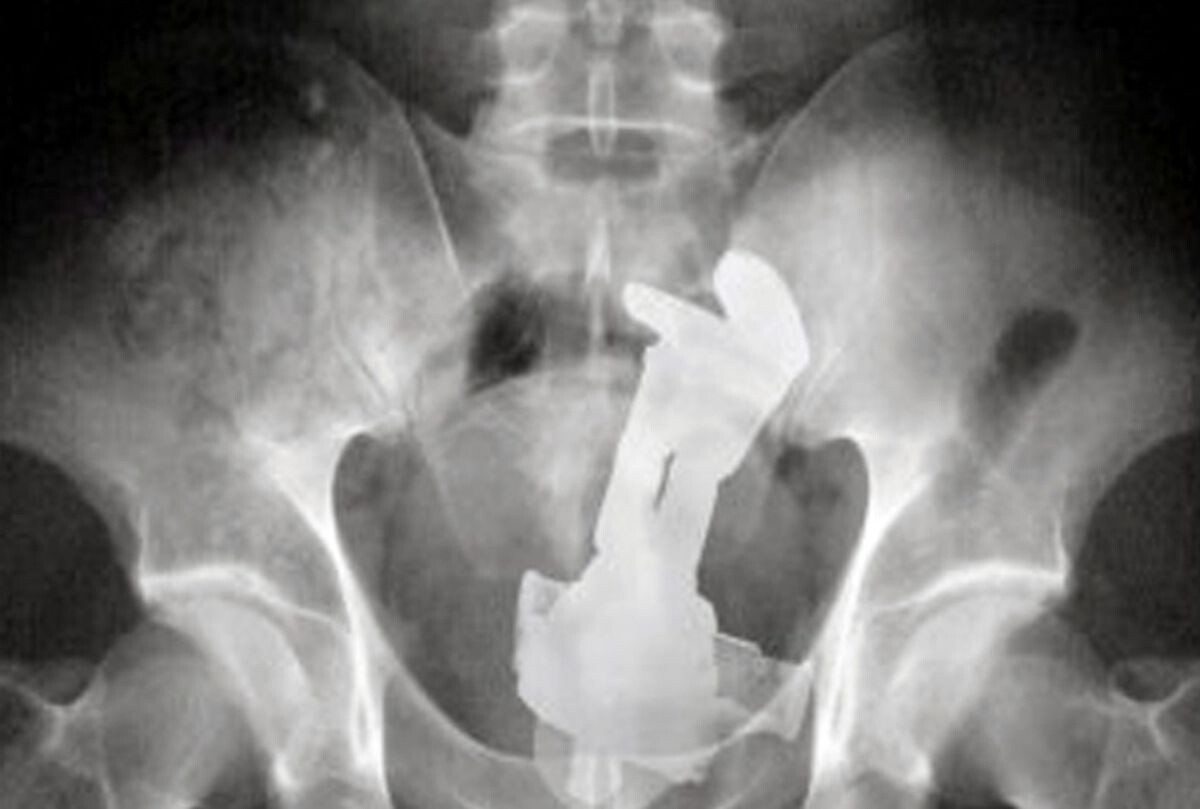

足から入れたのか

ワンチャン赤ちゃんの可能性